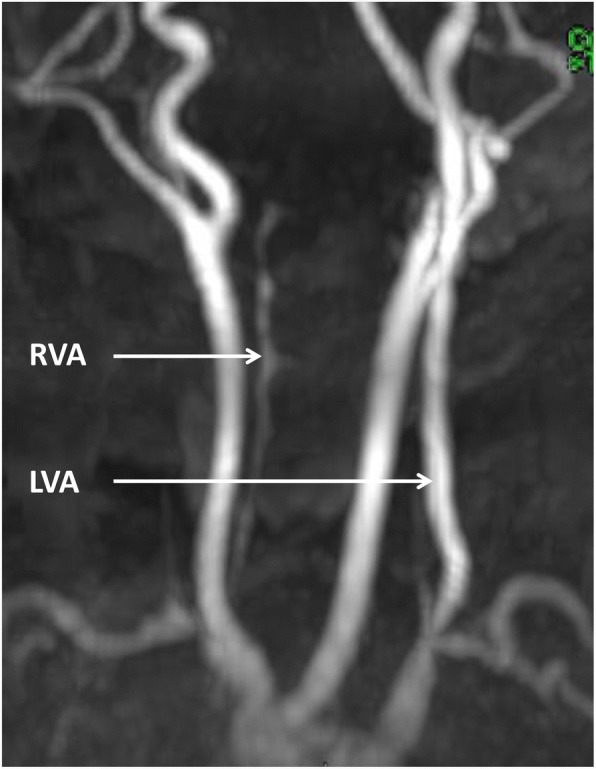

Fig. 3.

MR angiography showing hypoplasia and parietal irregularities of the V1 and V2 segments (white arrow) and agenesis of the V3 and V4 segments of the right vertebral artery (RVA). LVA: left vertebral artery

Focal lesions, whether associated or not with abnormalities of the vertebrobasilar arterial system, have led to the alternative hypothesis of an acquired, i.e. disruptive, mechanism [19]. The previously described vascular abnormalities in brainstem disconnection were mainly the absence or the extreme hypoplasia of the vertebral or basilar arteries [20]. In our case, MR angiography demonstrated hypoplasia and parietal irregularities of the proximal segments and absence of the distal segments of the right vertebral artery. The unilateral, well-defined, elliptical anteroposterior lesion of the cervico-medullary junction in our patient may be consistent with intrauterine ischaemia, but the precise timing of the insult is difficult to establish. During the early embryonic period, the posterior circulation is exclusively supplied by the internal carotid arteries through a series of anastomoses that will regress with the development of the vertebrobasilar arterial system [25]. The trigeminal, otic and hypoglossal arteries intervene in the formation of the basilar artery. The cervical portion of the vertebral artery, i.e. the V1 and V2 segments, is formed by anastomoses from the first six cervical intersegmental arteries, while the proatlantal intersegmental artery contributes to the formation of the V3 and V4 segments. In our patient, the lack of visualization of the V3 and V4 segments of the right vertebral artery on MR angiography may be explained by early occlusion or agenesis of the proatlantal artery. However, the origins of these vascular abnormalities may also be dysplastic or inflammatory, in parallel with the vascular involvement observed as early as 12 weeks of gestation at the level of placenta. Moreover, the resulting ischaemia may have caused the focal defect at the medullary level, the homolateral hypoplasia of the exo-occipital bone, and the lateral mass of C1. Indeed, these last two elements probably have a common embryological origin, from the fourth occipital and the first spinal sclerotomes, and they are also perfused by the proatlantal artery [26]. The hypoplasia of the right transverse process of C2 might be related to the hypoplasia of segments V1 and V2, its blood supply being provided by the first intersegmental cervical artery [27]. Other causes of disruptions, such as alcohol or cocaine exposure during pregnancy, have also been described in brainstem disconnection [28, 29]. Nevertheless, the controversy concerning a malformative or vascular origin of this condition has not yet been resolved. The involvement of genes critical for both the formation of the brainstem and its vascularization should also not be excluded [22].